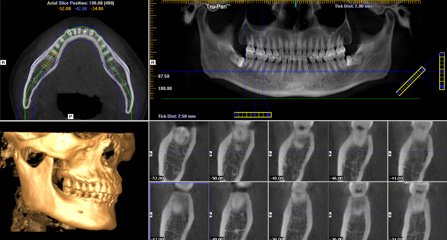

博愛牙科着眼于全鏈條的數字化診療解決方案,與德國Kavo、瑞典Nobel、韓國奧齒泰、中國康泰健等國際知名齒科品牌合作,建立“深圳數字化口腔聯盟”,應用全數字化口腔模式,從CBCT數據提取、AI口掃取模、AI智能口腔體檢、數字化分析模拟與方案設計、3D打印、CAD/CAM椅旁加工以及手術模拟導航等,全流程打通數字化口腔精确診療的各個環節,實現博愛數字化口腔診療體系新升級。

三维影像数据 一次性精确采集

数据云端整合 智能方案模拟

动态导航监测 精确控制植入路径